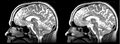

Original file(1,162 × 426 pixels, file size: 323 KB, MIME type: image/png)

Registration of a t2w image to arbitrary t1 and back via BSpline Registration module.

current15:07, 21 April 2009Thumbnail for version as of 15:07, 21 April 20091,162 × 426 (323 KB)Rauscha (talk | contribs)Registration of a t2w image to arbitrary t1 and back via BSpline Registration module.